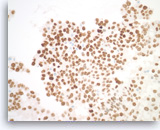

Pancreatic endocrine neoplasm #1,

Pancreas FNA, Cell Block.

The synaptophysin immunostain shows cytoplasmic positivity in the tumor cells, indicative of neuroendocrine differentiation.

40X

Pancreatic endocrine neoplasm #1,

Pancreas FNA, Cell Block.

The synaptophysin immunostain shows cytoplasmic positivity in the tumor cells, indicative of neuroendocrine differentiation.

40X

Pancreatic endocrine neoplasm #1,

Pancreas FNA, Cell Block.

The tumor cells are also positive for chromogranin, another neuroendocrine marker, with a granular cytoplasmic staining pattern.

40X

Pancreatic endocrine neoplasm #1,

Pancreas FNA, Cell Block.

The tumor cells are also positive for chromogranin, another neuroendocrine marker, with a granular cytoplasmic staining pattern.

40X